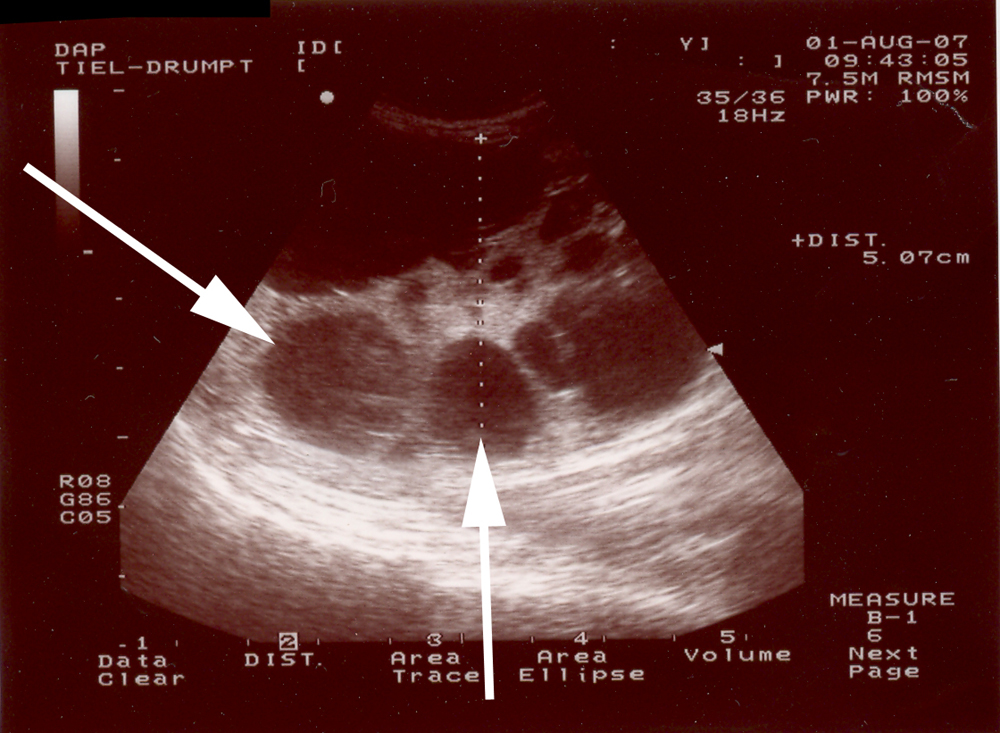

Polycystic Kidney Disease (PKD)

Er zijn meerdere cysten vanaf de geboorte in de beide nieren aanwezig. Ze komen zowel in het niermerg als in de nierschors voor. De cysten verdringen, terwijl ze groter worden, het normale nierweefsel.

Voor de preventie zijn alleen foktechnische maatregelen mogelijk. Hiervoor dien je te weten welke katten dragers zijn. Tot nu toe kon dat bekeken worden met de echo vanaf 4 weken leeftijd. Er konden helaas cysten gemist worden wanneer deze heel klein waren.